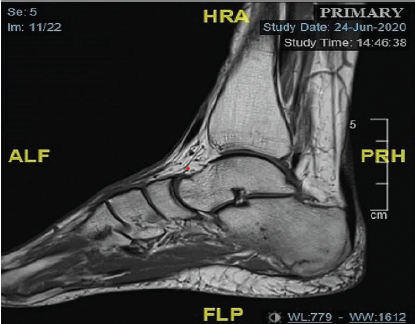

Massive Tendo Achilles Xanthoma Treated with en bloc Excision and Reconstruction with Flexor Hallucis Longus Tendon Transfer: A Case Report

Maheshwar Lakkireddy , Srikanth Eppakayala , Deepankar Satapathy , Deepak kumar maley , Syed Ifthekar

………………………………p.199-203